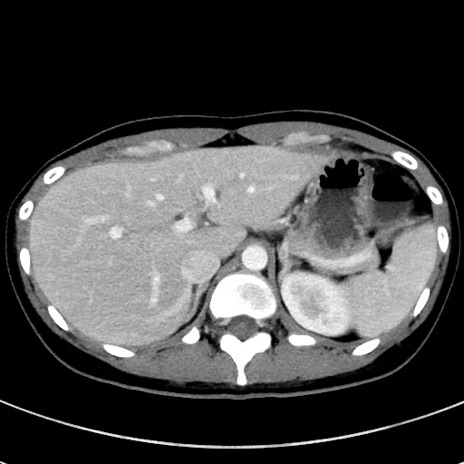

症例17(横断像)

【症例】20歳代女性

【主訴】嘔吐、下腹部痛

【現病歴】昨日夕食後に嘔吐し下腹部痛が出現。本日になっても嘔吐持続し改善しないため来院。

【身体所見】意識清明、BT 37.2℃、BP 108/67mmHg、腹部:平坦、やや硬、下腹部正中から右にかけて圧痛あり、反跳痛軽度あり、tapping pain(+)。

【データ】WBC 13600、CRP 14.94